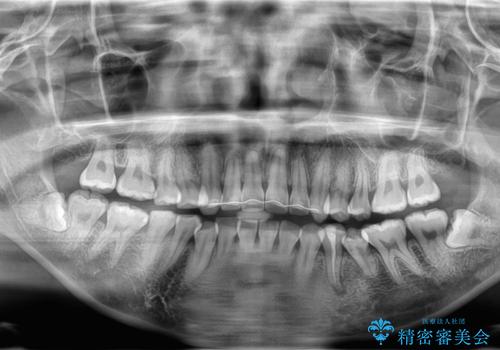

親知らず抜歯

- 20代女性

- 親知らずを抜きたいとのことで来院。CTで神経の位置などを確認し、抜歯を行いました。1週間後には抜糸に来院予定です。

しっかり麻酔が効いていることを確認し抜歯を行いました。